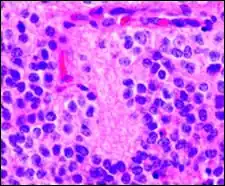

Micrograph of perivascular pseudorosettes

A perivascular pseudorosette consists of a spoke-wheel arrangement of cells with tapered cellular processes radiates around a wall of a centrally placed vessel. The modifier “pseudo” differentiates this pattern from the Homer Wright and Flexner-Wintersteiner rosettes, perhaps because the central structure is not actually formed by the tumor itself, but instead represents a native, non-neoplastic element. Also, some early investigators argued about the definition of a central lumen, choosing “pseudo” to indicate that the hub was not a true lumen but contained structures. Nevertheless, this pattern remains extremely diagnostically useful and the modifier unnecessarily leads to confusion. Perivascular pseudorosettes are encountered in most ependymomas regardless of grade or variant. As such, they are significantly more sensitive for the diagnosis of ependymomas than true ependymal rosettes. Unfortunately, perivascular pseudorosettes are also less specific in that they are also encountered in medulloblastomas, PNETs, central neurocytomas, and less often in glioblastomas, and a rare pediatric tumor, monomorphous pilomyxoid astrocytomas.[2]